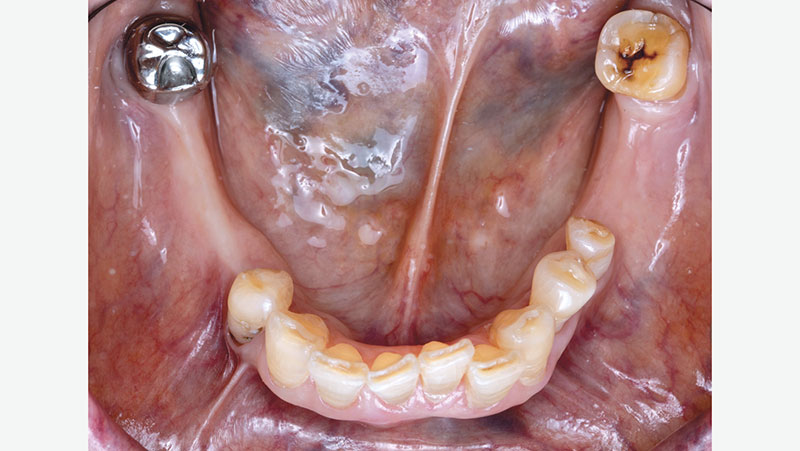

For existing partials, examine the occluding tooth contact, the position of the tongue, how the retentive and reciprocal arms are placed, and how it rests on the occlusal surface of the crown. Be sure to also examine the patient’s oral environment when the partial is removed, noting the spacing and the gingival region around the crown.

Original-crown-without-partial

Original crown without partial

Partial-over-original-crown

Partial over original crown